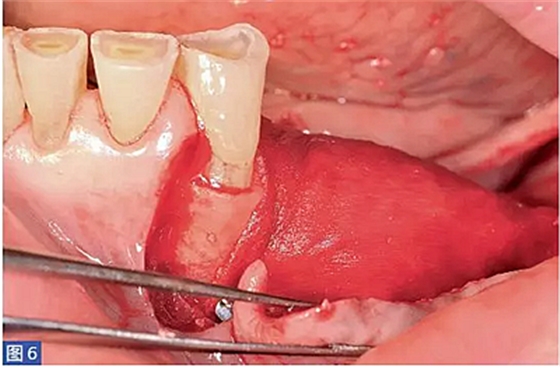

圖6:(左側(cè))病例1. 用鈦釘固定膜。